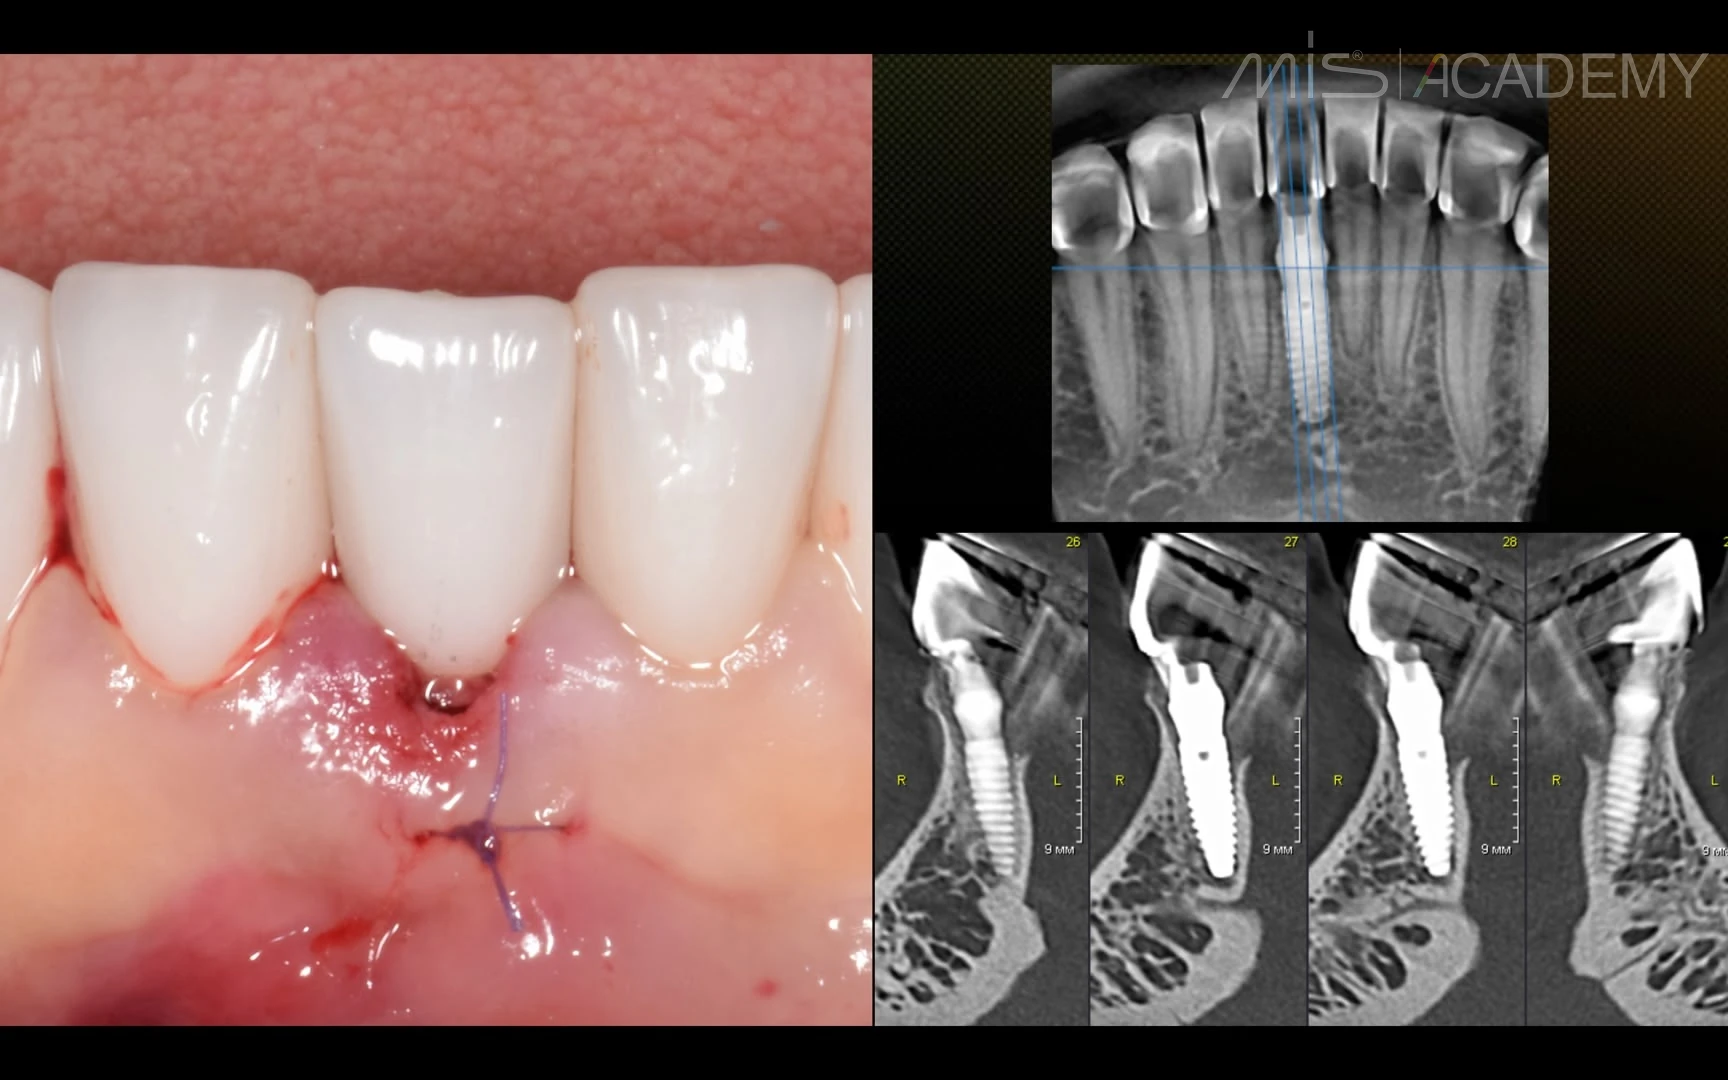

Интересный клинический случай с восстановлением костной ткани язычно в области зуба 4.1.

5 месяцев назад пациентка обратилась с жалобами на боль при накусывании на 4.1 зуб и отёк с язычной стороны.

Проведено:

— Удаление зуба 4.1 по причине трещины корня, кюретаж лунки;

— Установка имплантата MIS C1 диаметром 3,3;

— CONNECT абатмент высотой 3,0;

— Пластика десны с обеих сторон;

— Bio-oss, стимул-осс,

— Временная коронка.

Результат через 5 месяцев — полное восстановление язычной стенки альвеолярного отростка. Замена временной коронки на постоянную циркониевую с полированной поддесневой частью.